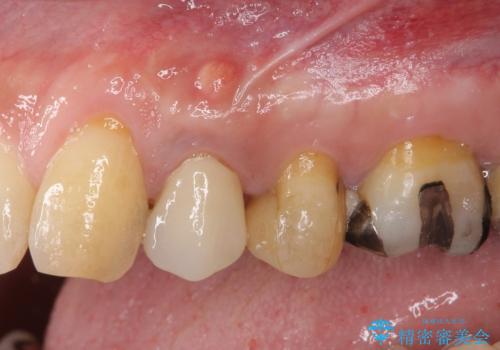

顕微鏡下で診察を行ったところ、歯根が垂直に破折していたため、抜糸してインプラントによる補綴治療を行うこととしました。

ジルコニアカスタムアバットメントは、歯肉ラインに金属が見えにくいというだけでなく、クラウンを装着する土台の形が天然歯と近い形態となるため、清掃性が高く歯肉が腫れにくいというメリットがあります。

インプラントは、人工骨を用いた際の骨誘導能が比較的高いとさせるストローマン社のSLActiveを使用しました。